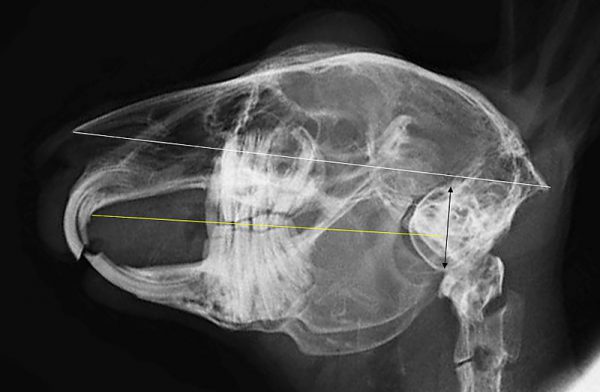

基本的には切歯を肉眼で観察し、口の中に耳鏡などを入れて臼歯を観察します。ただし目視で観察できるのは歯肉から出ている歯冠のみで歯根は見れません。

歯根はX線検査をで評価をしますが、左右、上下が重なっての評価になり、全ての異常を確認することはできません。

正確に診断するにはCT検査が必要になります。ウサギは無麻酔で撮影が可能です。